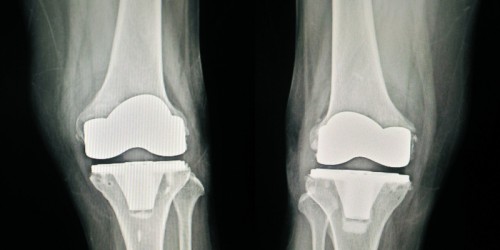

Re. Oxford knee procedures...eleven years ago I had both knees done at the same time. Awful post op pain that was poorly managed by The Number One Oxford surgeon in a major Midwest city. I returned at five years for a long term follow up, stated ongoing discomfort, especially after golf. X-Rays were fine so the knees were fine thank you very much. Continued to struggle with periodic cortisone shots in a new city with a new doc. Current xrays show major wear on the plastic slide and some loosening from the bone. He wondered why the Oxford was used since I am quite bow legged and there is a lot of pressure on the joint. Even so, we walk 4-5 miles a day, then elevate and thank goodness for tramadol. But....come Friday a total knee is going in with the other one likely being done within the next year. I was told they should last close to 20 years. My advice to anyone considering them is to do your research better than I did. Probably not a good choice if your legs are not real straight. And....if arthritis is an underlying issue, it will likely not be eliminated by a partial and may well continue into the rest of the knee-over time of course-and might require a total revision at some time. And, if you decide on an Oxford, get a surgeon who does a bunch of them and ask them about their rate of success and how many require revision surgery. Best wishes to anyone who needs knee replacement...